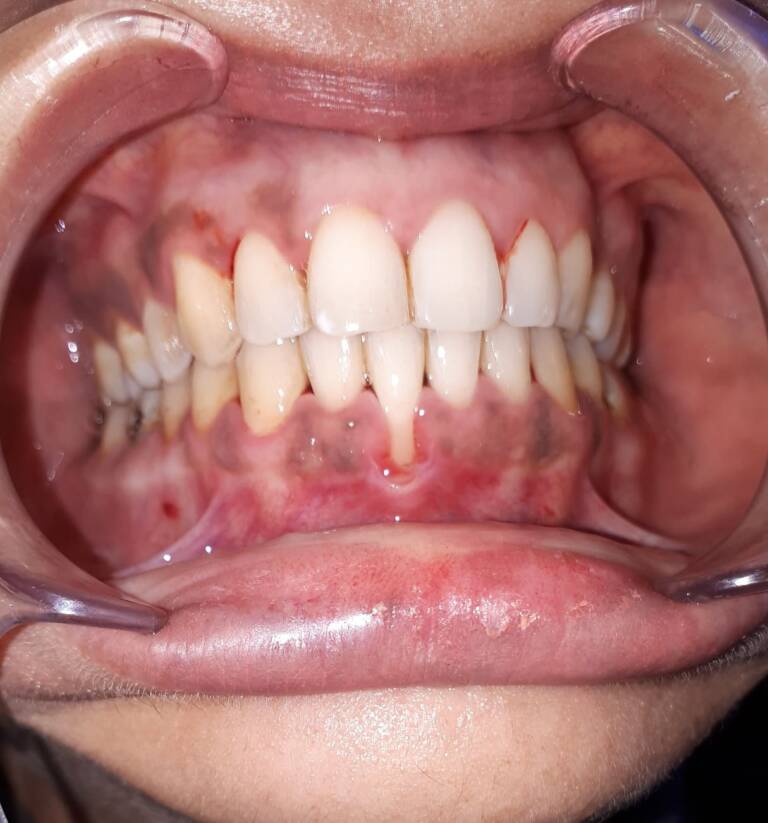

Source: winskinstgo.pages.dev Gingival detachment and recession Bücco , Trous noirs dentaires : comprendre les causes, conséquences et traitements pour un sourire éclatant Les triangle noirs entre les dents dûs à la rétraction gingivale, sont très inesthétiques

Source: zudemoecn.pages.dev L'écart entre l'avant et les autres dents comment réparer et enlever un trou , Ceux-ci peuvent avoir plusieurs origines - par exemple la récession gingivale ou la perte de papille - et peuvent être traités de différentes façons Chez certains patients, on peut observer des triangles noirs entre les dents

Source: lscareiva.pages.dev Extrême détartrage de dents Vidéo Dailymotion , Les triangles noirs, ou embrasures gingivales ouvertes, sont des espaces qui peuvent étonnamment apparaître entre les dents après un nettoyage dentaire de routine ou un détartrage Alors que les patients s'attendent à quitter le cabinet du dentiste avec des dents plus propres et plus saines, l'apparition de ces espaces triangulaires sombres peut être inquiétante.

Source: picupalscld.pages.dev Détartrage des dents fait maison avec vinaigre blanc et citron Détartrage des dents , Les triangles noirs, ou embrasures gingivales ouvertes, sont des espaces qui peuvent étonnamment apparaître entre les dents après un nettoyage dentaire de routine ou un détartrage Ceux-ci peuvent avoir plusieurs origines - par exemple la récession gingivale ou la perte de papille - et peuvent être traités de différentes façons